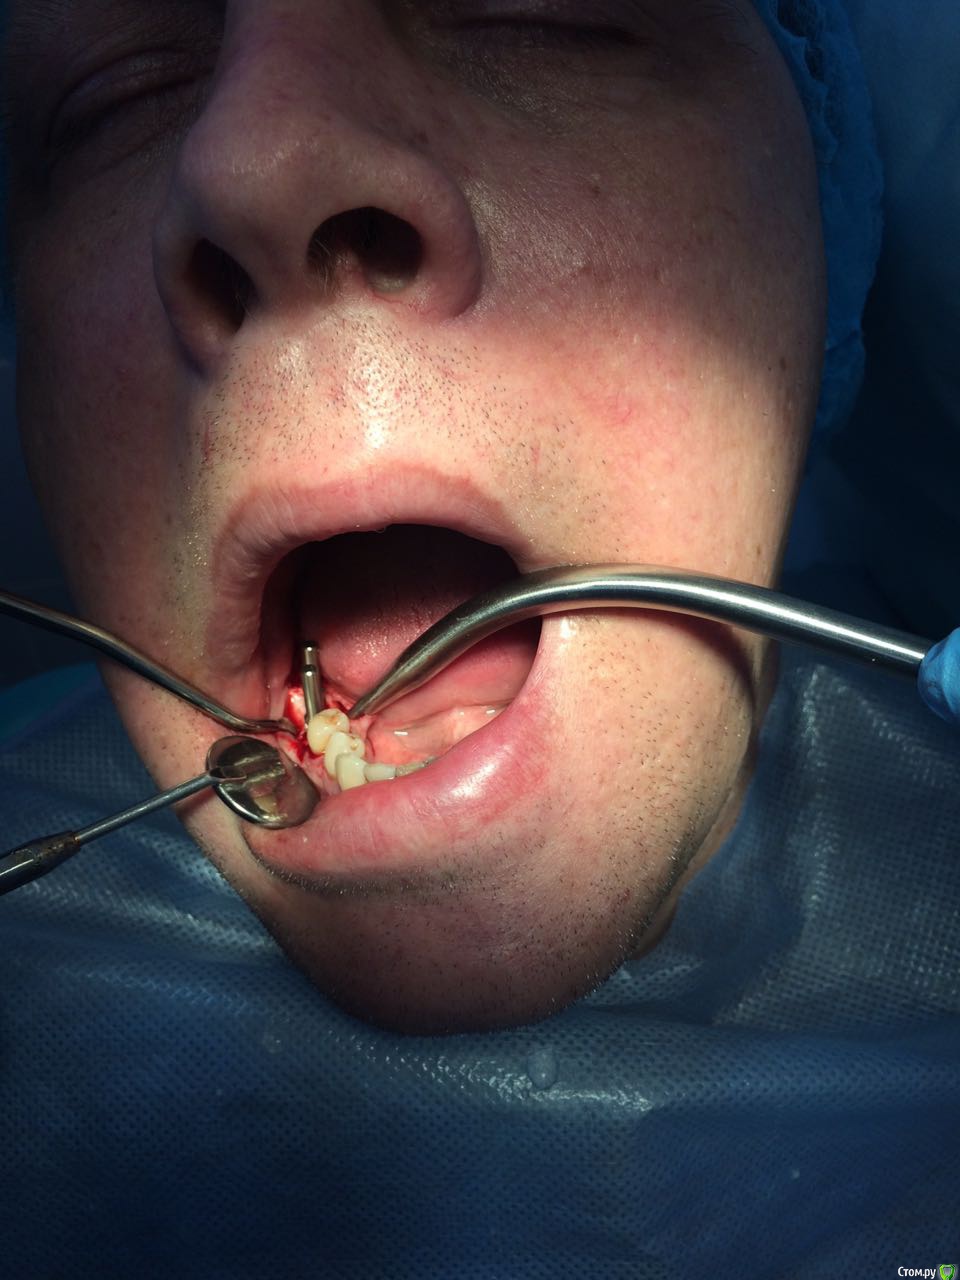

Пациент с жалобами на отсутствие 47 разрушение 46,48. После совещания с ортопедом и терапевтом принято решение удалять 46,48 и устанавливать импланты в позицию 46,47. post-48560-0-74269200-1490419709_thumb.jpgpost-48560-0-43642200-1490419772_thumb.jpgПрисутствует парадонтоз, лечение у пародонтолога прошел заранее. Решено было 46 ставить одномоментно, с графтом и мембранкой, 47 по стандартному протоколу, импланты alpha bio aic 4,2*12, 4,2*10 соответственно. post-48560-0-27512000-1490420040_thumb.jpgpost-48560-0-53003700-1490420066_thumb.jpg Сначала удалил, атравматично с распилом по бифуркации.post-48560-0-43340000-1490420143_thumb.jpgpost-48560-0-35881400-1490420170_thumb.jpgРаскрылся над 47, подготовил ложе, пины параллельности. Здесь вопрос, думаю зря широко отслоился и затронул 46?post-48560-0-32979400-1490420293_thumb.jpgpost-48560-0-94312700-1490420324_thumb.jpgустановка имплантов с фдм, графт в лунки 46 апатос, мембрана Эва. Снять не получилось. Нить моно 5-0. Тут опять вопрос фдм нужно было ставить шире? Но опять же импланты заглубил немного...post-48560-0-50977700-1490420493_thumb.jpg и контрольный. Конструктивная критика приветствуется)))

Фото надо обрезать. У Вас вестибулярный дефект одномоментно с графтом у 46 -лучше законсервировать лунку. 47 также дефицит тканей вестибулярно-сст на узкий фдм. Это какой-то новый альфабио? Я бы не оставлял такой формирователь на весь срок интеграции. На 47 ,судя по всему,фдм не сел,уступ мешает.